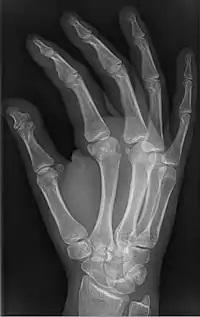

| Brachyphalangy of the thumb's distal phalanx, also known as brachydactyly type D, with otherwise normal phalanges of the 2nd-5th digits | |

Brachyphalangy is a condition in which one or more of the phalanges of the fingers and toes are smaller than normal.[1]

This condition is one of the most common non-syndromic causes of brachydactyly and clinodactyly.